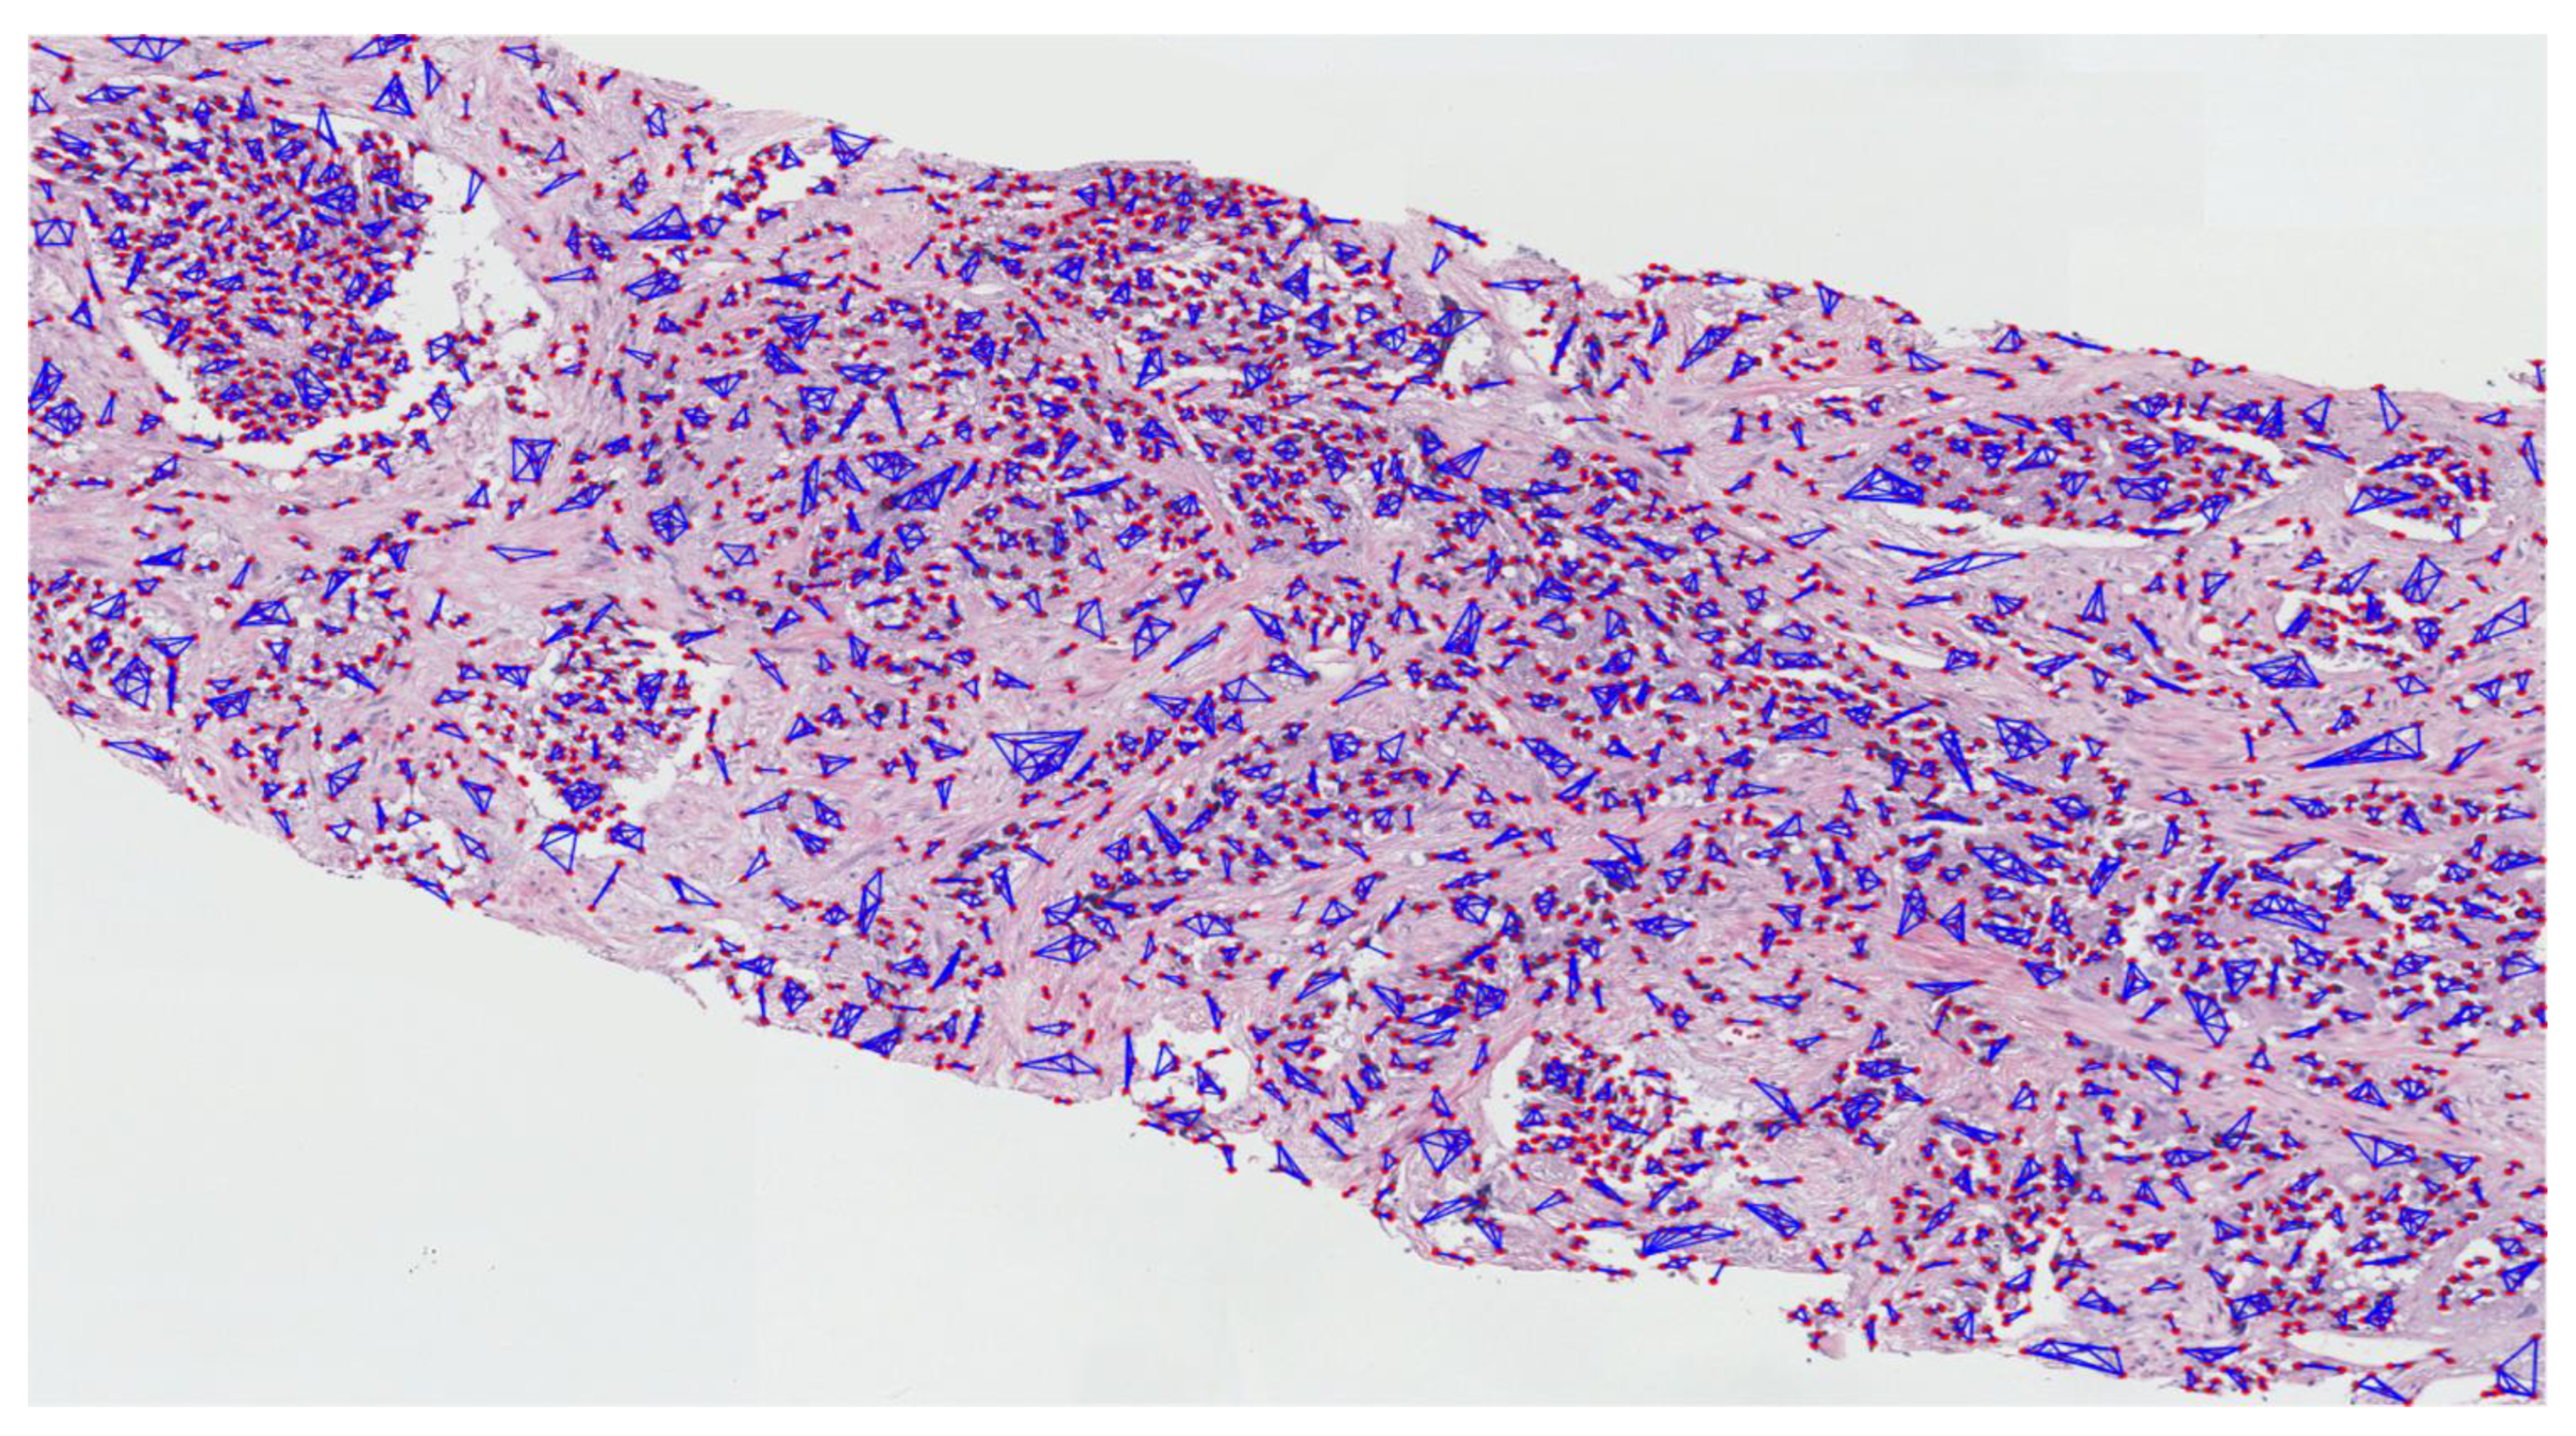

3.2.2. Nuclear Segmentation of Cancer Cells

3.2.3. Cluster Analysis